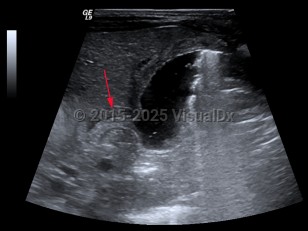

EchinococcosisEchinococcosis

Ureteral calculus